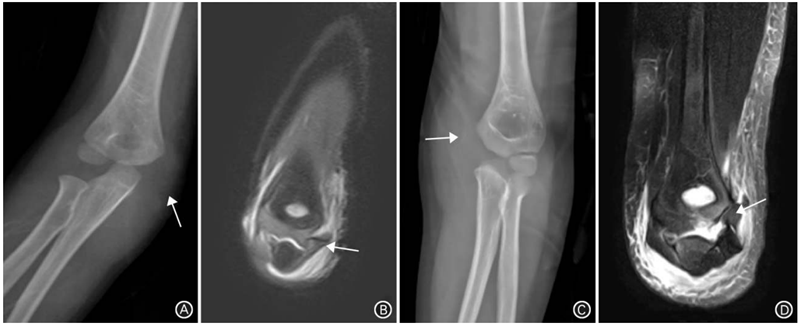

图2 肱骨内髁骨折。A.正位X线片示内侧软组织较外侧明显肿胀影(箭头所示),未见“C”形骨折片,容易漏诊;B.冠状位MRI示肱骨内髁撕脱软骨骨块;C.正位X线片示内侧软组织较外侧明显肿胀影,可见一薄“C”形骨折片(箭头所示),易漏诊;D.冠状位MRI示肱骨内髁撕脱翻转180°软骨骨块,累及关节滑车(箭头所示)